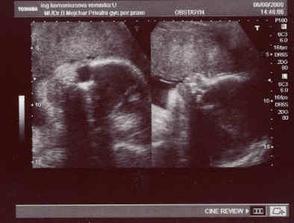

4.6. - opět kontrola a další UTZ (další screaning) - Zdenda byl tentokrát v ordinaci s námi!!! pan doktor nám natočil i DVD....miminko se na UTZ krásně vrtělo a pak nám pan doktor prozradil, že to bude asi holčička 🙂)...